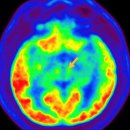

떨림, 자세이상, 경직, 보행이상, 수면장애, 떨림(진전), 서동관련질환비정형 파킨슨 증후군, 이차성 파킨슨증, 알츠하이머병진료과신경과동의어파킨슨질환,퍼킨슨병,특발파킨슨병 질환설명 의료진 AMC병법 뉴스룸 정의 파킨슨병은 뇌간의 중앙에 존재하는...

Atypical Parkinsonism)증상자세 불안정, 자세이상, 보행이상, 근육강직, 떨림(진전), 서동관련질환파킨슨병, 이차성 파킨슨증, 알츠하이머병진료과신경과동의어진행핵상마비,다계통 위축,피질 기저핵 변성,루이소체치매 질환설명 식사요법 뉴스룸 정의...